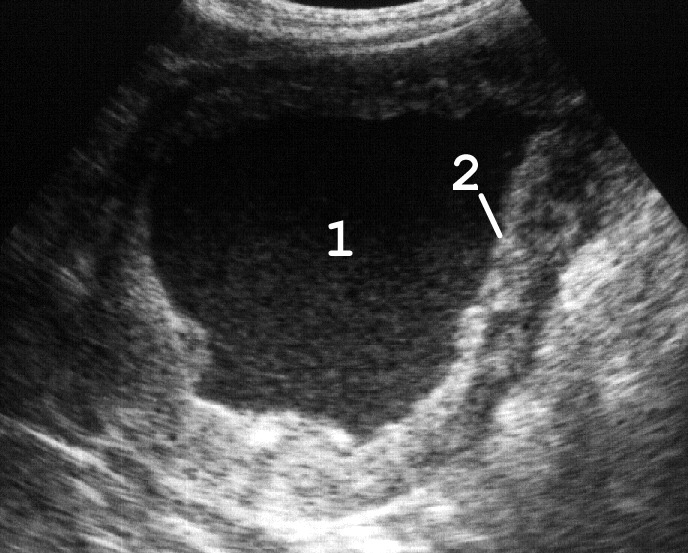

Уретероцеле может быть простым (при нормальном расположении устья) и эктопическим (при его эктопии), одно- и двухсторонним. Часто встречается уретероцеле одного из удвоенных мочеточников. При ультразвуковой цистоскопии уретероцеле обнаруживается как кистовидное расширение терминального отдела мочеточника, размеры которого изменяются при систоле и диастоле нижнего цистоида мочеточника (рис. 14).

Рис. 14. Сонограммы мочевого пузыря с уретероцеле: 1 − мочевой пузырь; 2 − уретероцеле; 3 − горизонтальный уровень эхогенного осадка при пиурии. (Поперечное сканирование, секторный датчик 5 МГц, “Siemens SL-1”).

Клинические проявления уретероцеле зависят от его размеров и степени нарушения уродинамики мочевых путей. Малые уретероцеле не нарушают оттока мочи, протекают бессимптомно и часто являются диагностическими находками. В большинстве же случаев уретероцеле приводит к развитию гидроуретеронефроза, который проявляется болевым синдромом. При уретероцеле больших размеров доминируют дизурические расстройства − рези, нарушение акта мочеиспускания. Застой мочи приводит к ее инфицированию и развитию хронического воспалительного процесса в мочевом пузыре и почках.